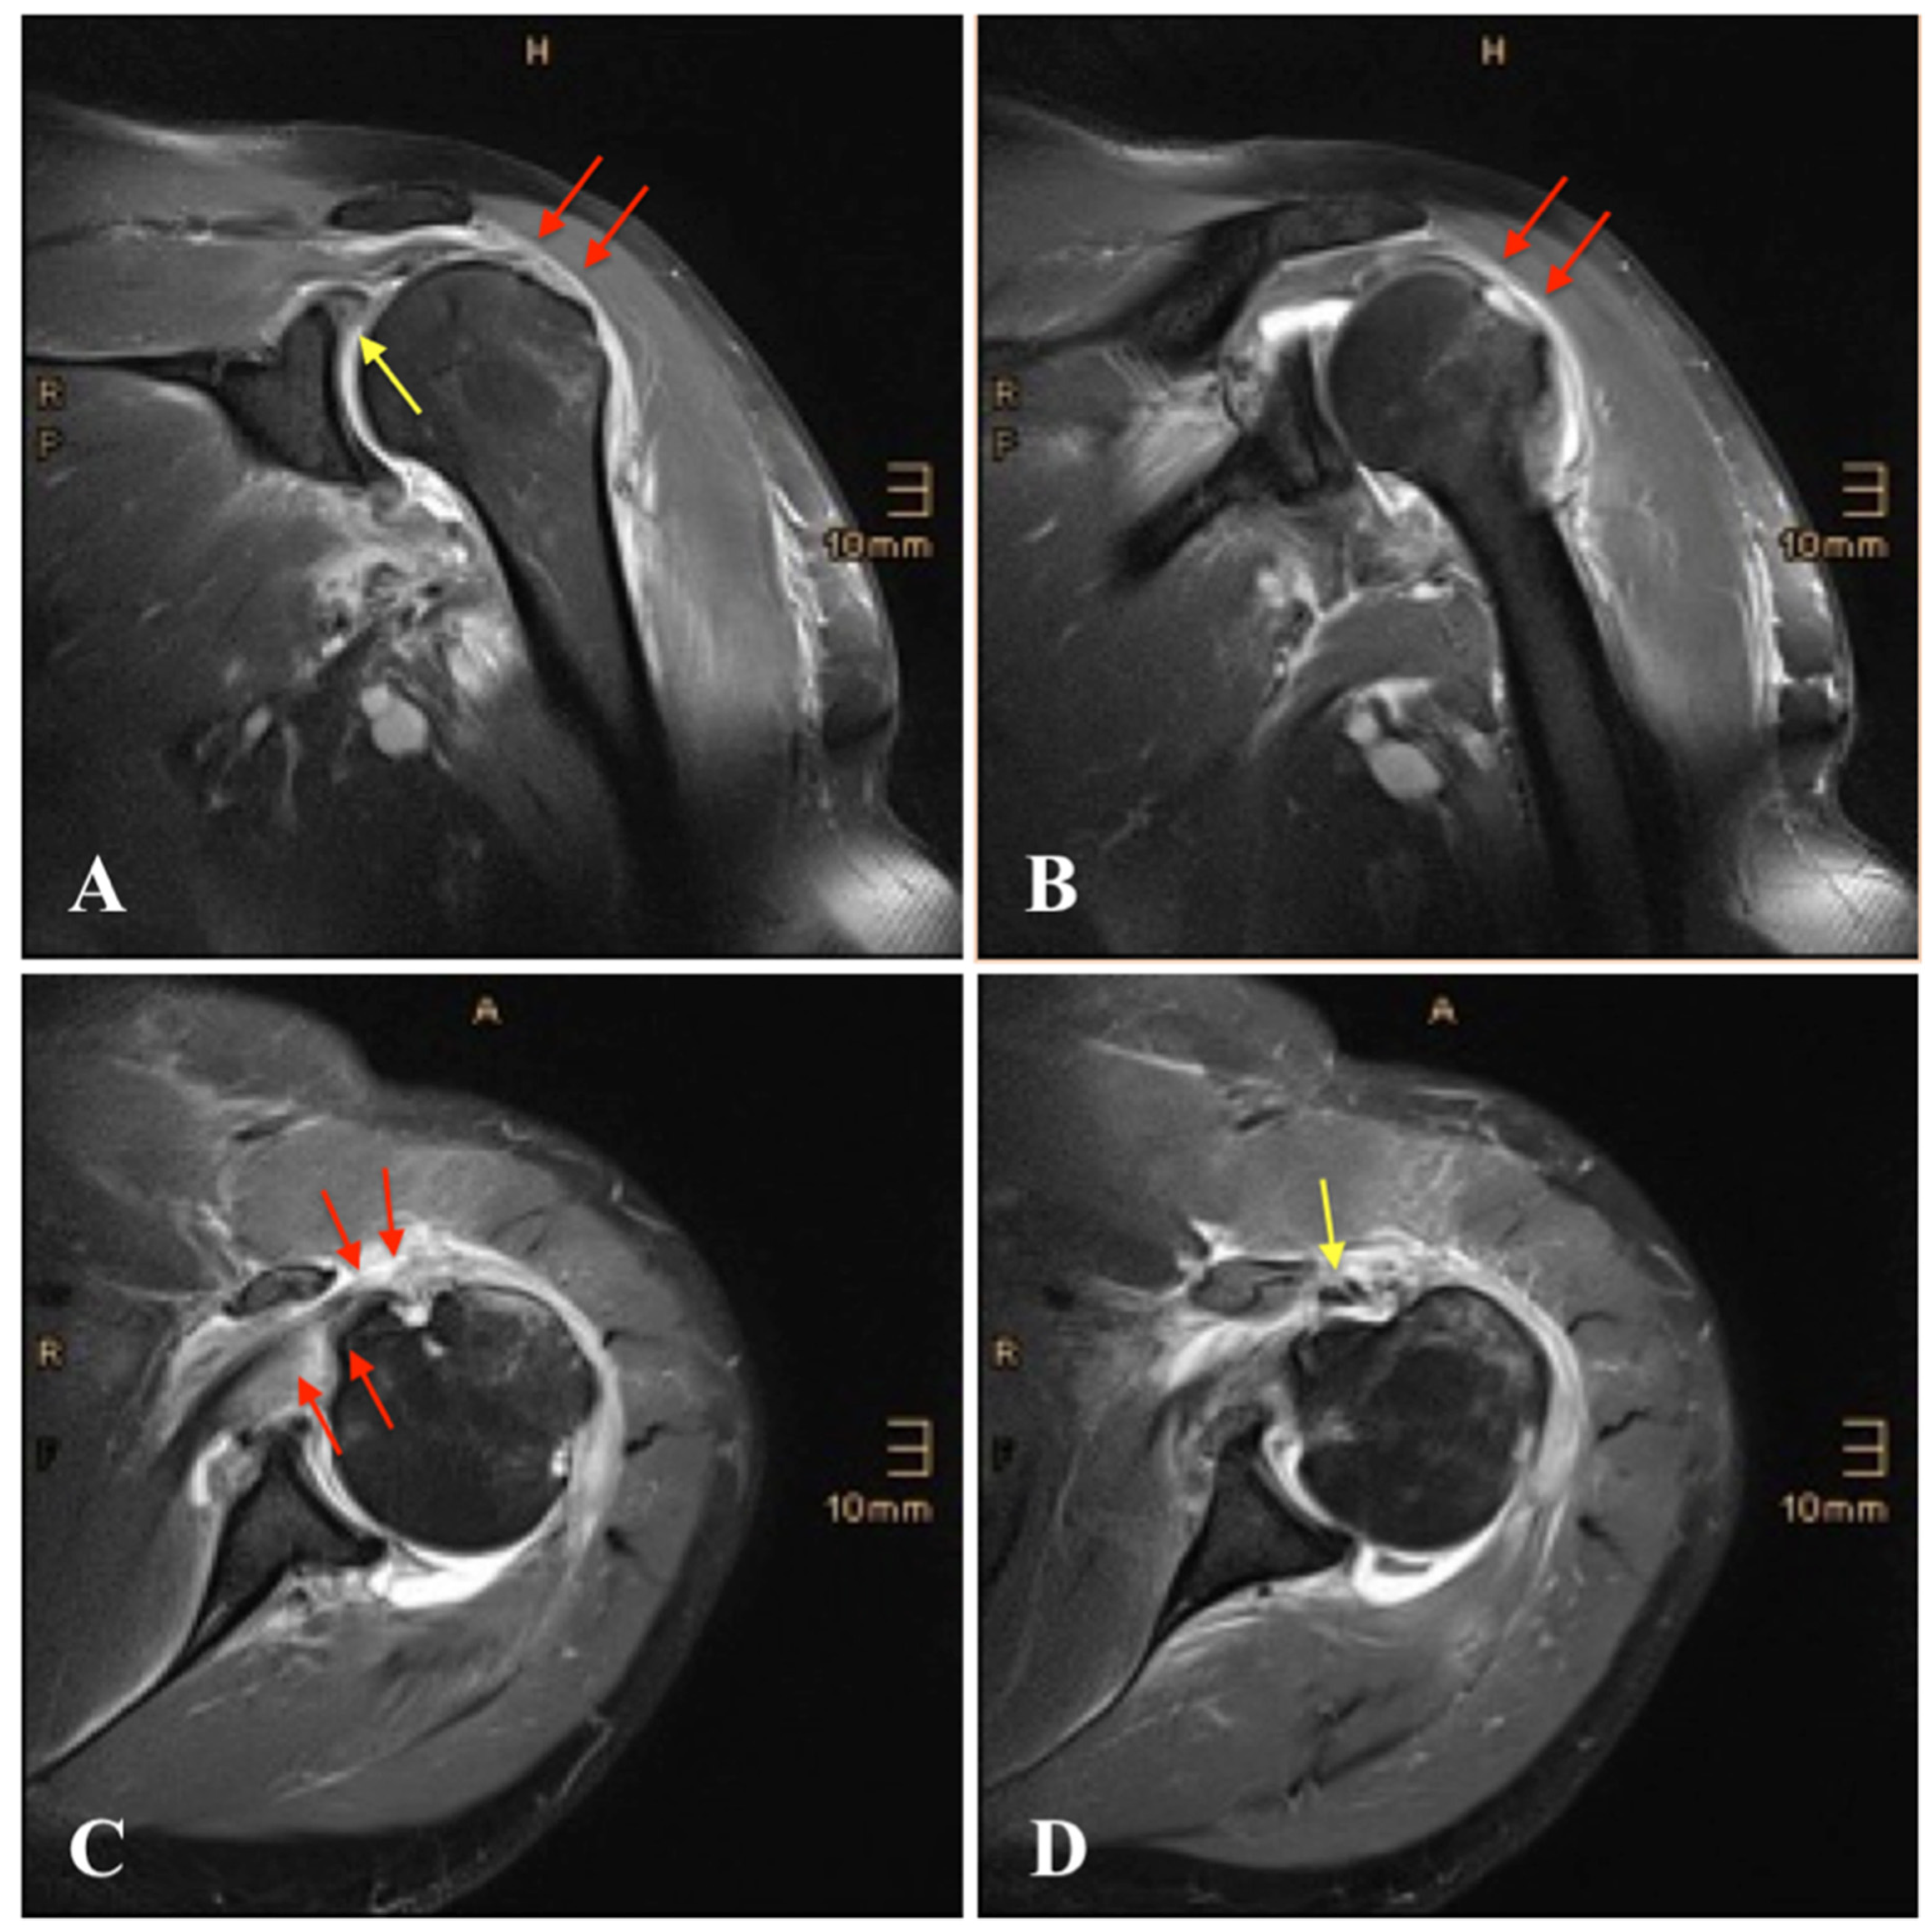

| 17 | Hill-Sachs lesion | - Rupture of the supraspinatus, - infraspinatus and subscapularis - tendon | - SLAP III lesion - Avulsion of posterior and inferior labrum | None | Arthroscopic rotator cuff repair, subacromial decompression and biceps tenotomy |

| 18 | Greater tuberosity fracture | None | None | None | None |